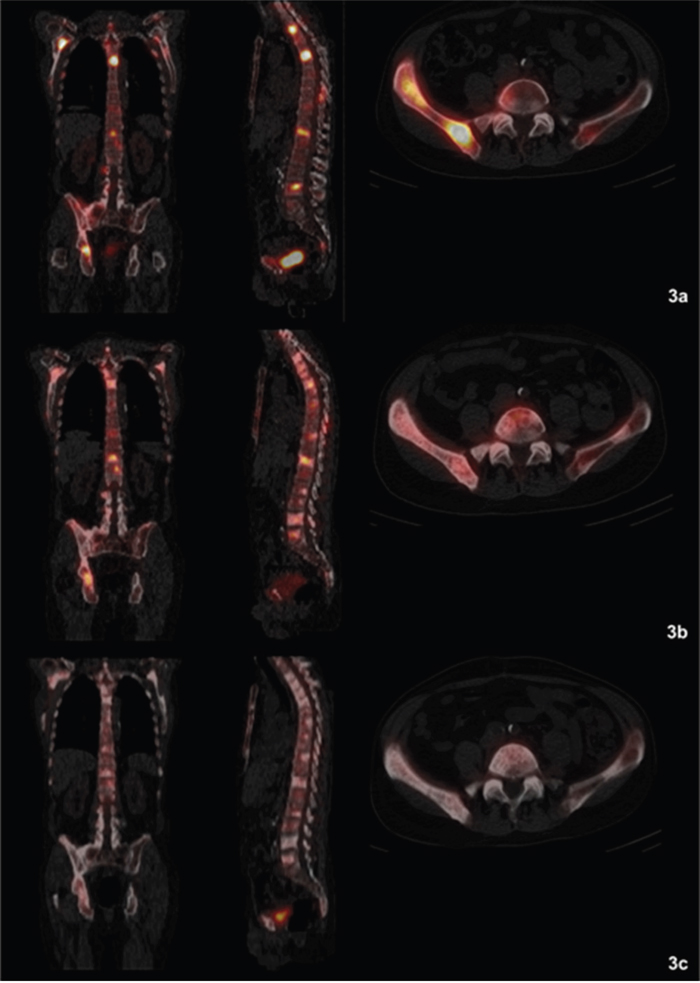

Three patients responded well to Ra-223 treatment with a decrease in extent of the disease (EOD) score (partial remission; patients 4, 5, and 8). In two of these patients (patients 4 and 5) ≥1 bone lesion was not visible anymore on BS during follow-up visit (Figures 2a-2c, 3a-3c). In four patients stable disease was documented after six cycles of Ra-223 (patients 2, 6 and 7), or after three cycles of Ra-223 (patient 3), respectively. Furthermore, progress of disease with an increase in EOD score was noticed in patient 1. In two patients (patients 9 and 10) BS was not performed due to early discontinuation of Ra-223 treatment.

Figure 3: (a-c) Fused Single Photon Emission Computed Tomography (SPECT)/CT images clearly depicting a decreasing radionuclide uptake in the bone metastases (patient 4). (a) (top row): SPECT/CT before start of therapy (before cycle 1): Evidence of disseminated bone metastasis with high radionuclide uptake. (b) (middle row): SPECT/CT during therapy (between cycles 3 and 4): Decreasing uptake in bone metastases. (c) (bottom row): SPECT/CT at follow-up visit: Significantly decreasing and missing radionuclide uptake in bone metastases compared to baseline images. No evidence of new bone lesions.